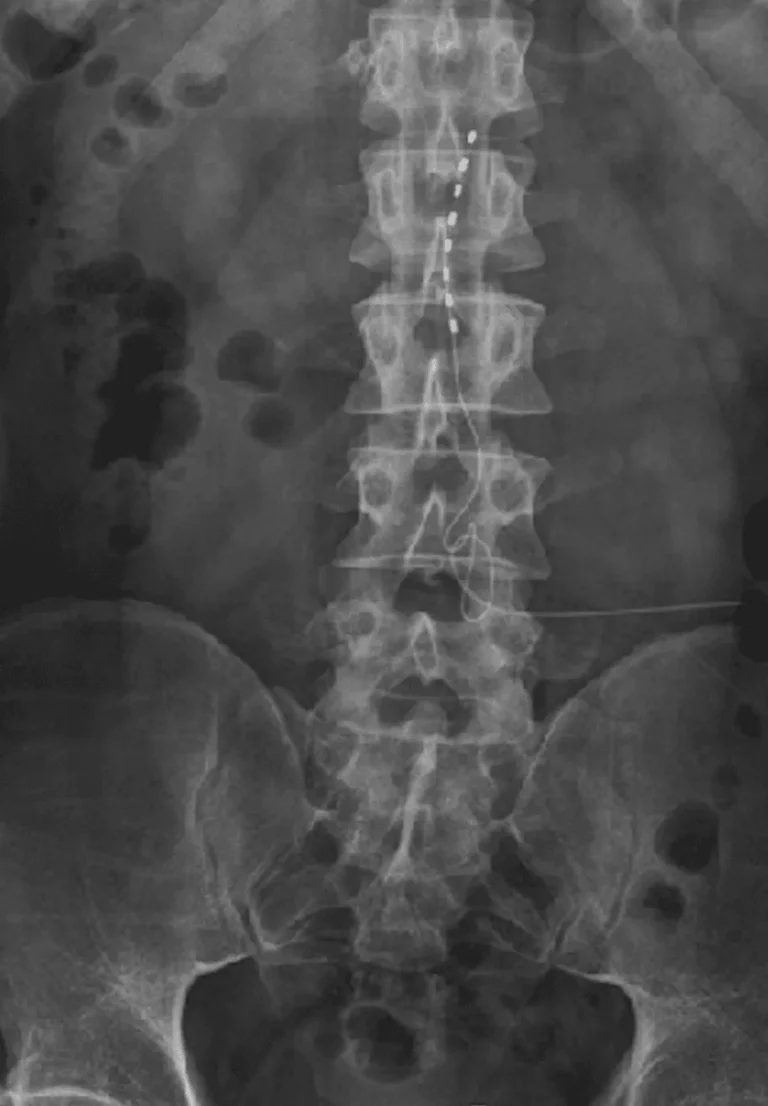

X-ray image showing a spinal cord with a series of electrode implants.

Spinal Instability

X-ray of a lower spine with metal implants and a medical device on the right side.

Back Pain Gets Worse

X-ray image showing a spinal column with a spinal cord stimulator implant.

Lead Migration

Implanted leads shift from their original position, causing loss of pain relief and requiring revision surgery.